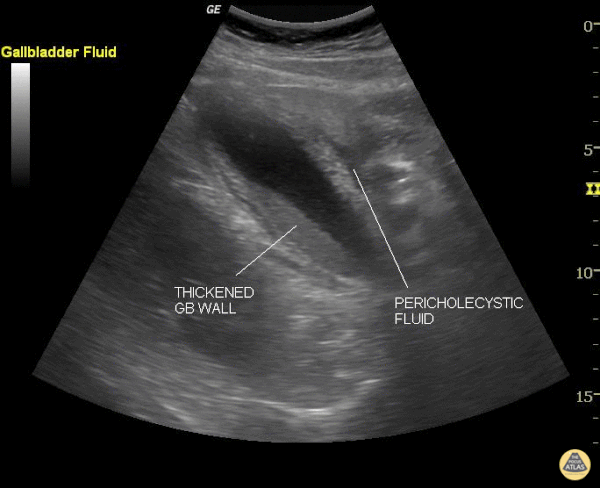

This still image shows two clear signs of acute cholecystitis. The gallbladder wall is thickened and there is pericholecystic fluid. Of note, when measuring the gallbladder wall it's better to measure the anterior wall as the posterior wall can appear enlarged due to artifact. The cut off for wall thickening is 3mm. The anterior wall is thickened in this case but is not labeled. Other signs to look for are stones, sludge, common bile duct dilatation, and overall gallbladder enlargement. Of note, a positive sonographic Murphy's carries a sensitivity of 63%, specificity of 93.6% and positive predictive value of 72.5%. Justin Bowra MBBS, FACEM, CCPU Emergency Physician, RNSH et al. (Sharon)